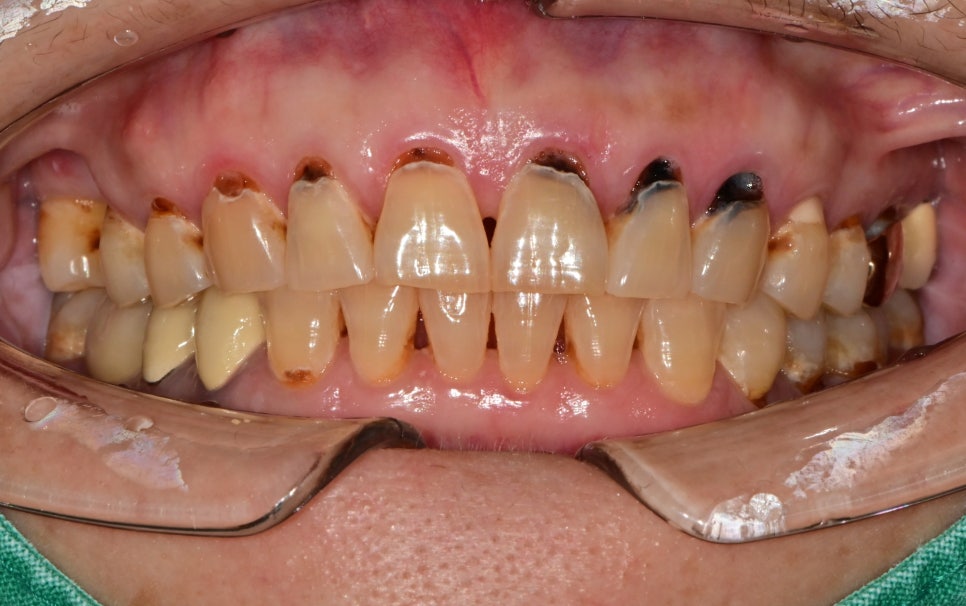

앞니 여러 군데가 까맣게 보여요

언제부턴가 잇몸과 치아 경계 부분이 파이고 까맣게 보인다고 내원해 주셨습니다.

초진 사진에서 보듯이 몇 군데는 치료가 되어있지만

특히 위쪽 앞니부터 작은 어금니까지 다수의 치아가 파여있고 충치가 생긴 상태입니다.